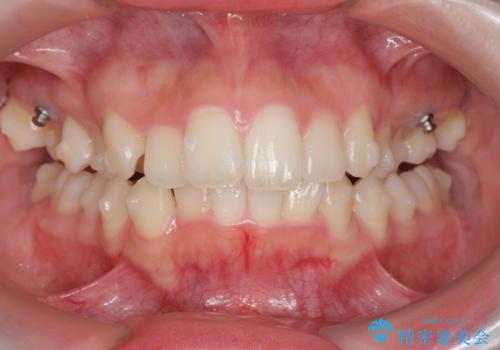

サクソフォン(アルト)の演奏で崩れてしまった歯並び、マウスピース矯正治療

- 高校時代の吹奏楽の部活でサクソフォン(アルト)を担当、「一生懸命練習をしすぎて気づいたら歯並びが悪くなっていた。矯正治療を受けたい!。」

とマウスピース矯正を希望され来院されました。

歯列の乱れが大きく難易度が高いため、

・治療期間の長期化が予想されること

・マウスピースで治り切らない場合ワイヤー矯正に変更すること

をご理解いただいた上でマウスピース矯正治療を計画します。

口腔内の清掃状態の良さに加えて、マウスピースを毎日きっちりと装着し、しっかりと使用していただけたことからワイヤー矯正は行わずにきれいに歯並びを治すことができました。

途中顎位が変わり、マイクロインプラントを併用した上顎臼歯の遠心移動が必要となったため治療が長期化しました。